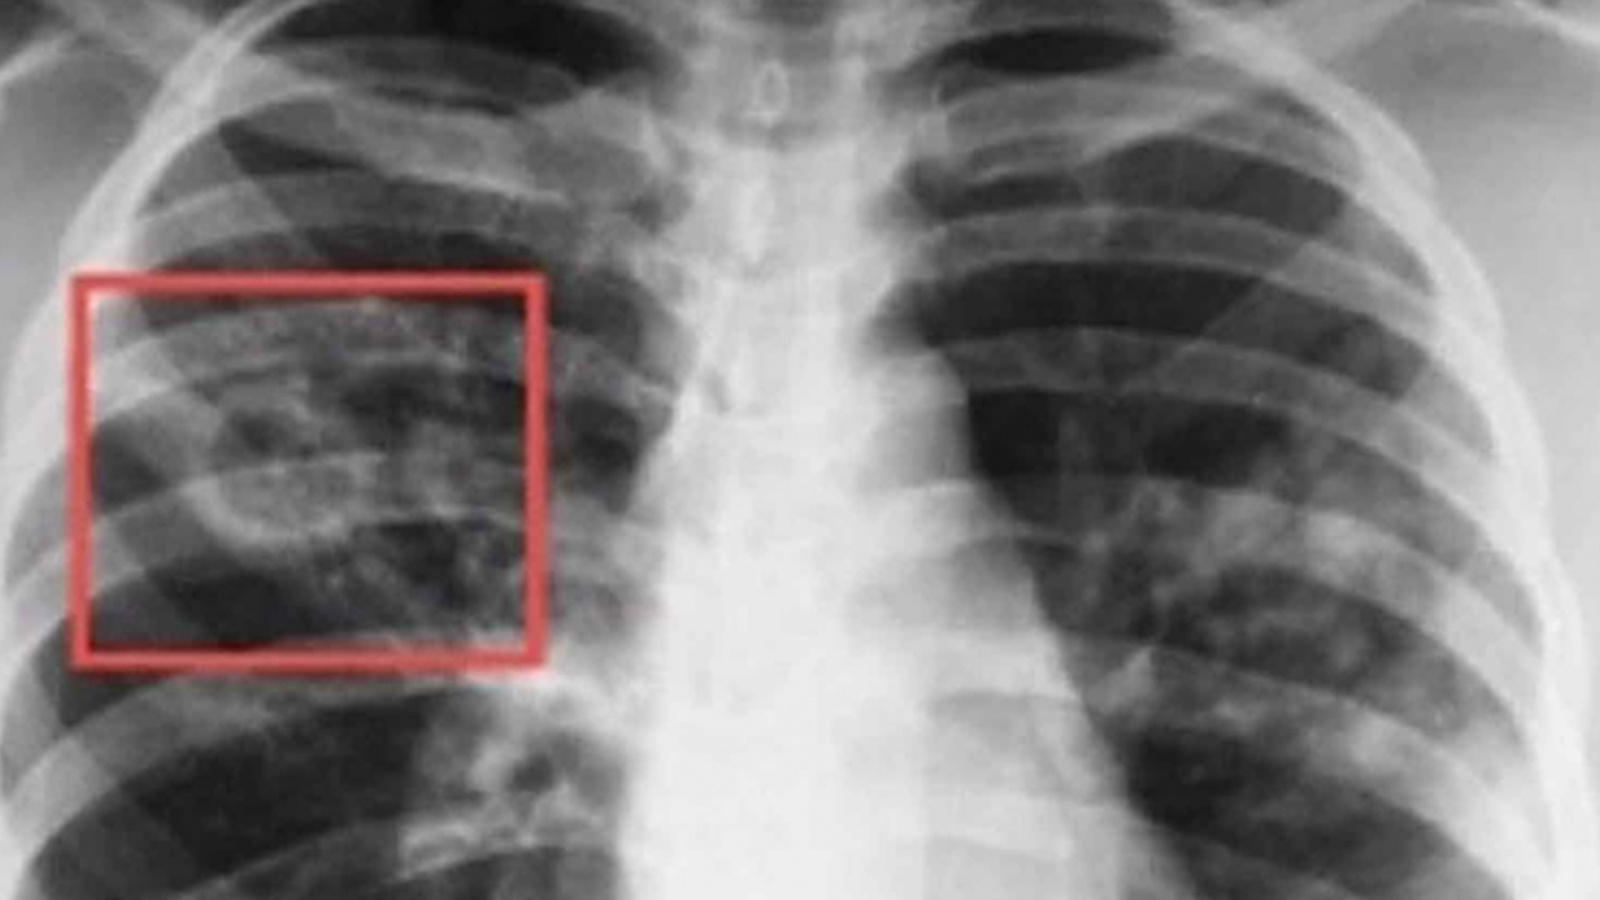

24 марта – Всемирный день борьбы с туберкулезом

Туберкулёз – тяжёлое инфекционное заболевание, распространена чаще всего лёгочная форма. Также туберкулёзом могут поражаться кости, суставы, глаза и как говорят мои коллеги – фтизиатры, все, кроме ногтей и волос. Чаще всего туберкулёзом болеют люди с ослабленным иммунитетом. Источником инфекции являются больной человек, крупный рогатый скот, который также болеет туберкулёзом.

Уважаемые жители г. Мамадыш и района! Приглашаем вас с целью профилактики и ранней диагностики туберкулёза, и других заболеваний легких, пройти флюорографическое обследование в больницу (обследоваться нужно не реже, чем 1 раз в год).

В ГАУЗ “Мамадышская ЦРБ” флюорография органов грудной клетки проводится ежедневно, понедельник - пятница, в кабинете № 139. Режим работы кабинета с 8.00-17.00 ч., перерыв с 12.00 -13.00 ч., суббота с 8.00-12.00 ч.